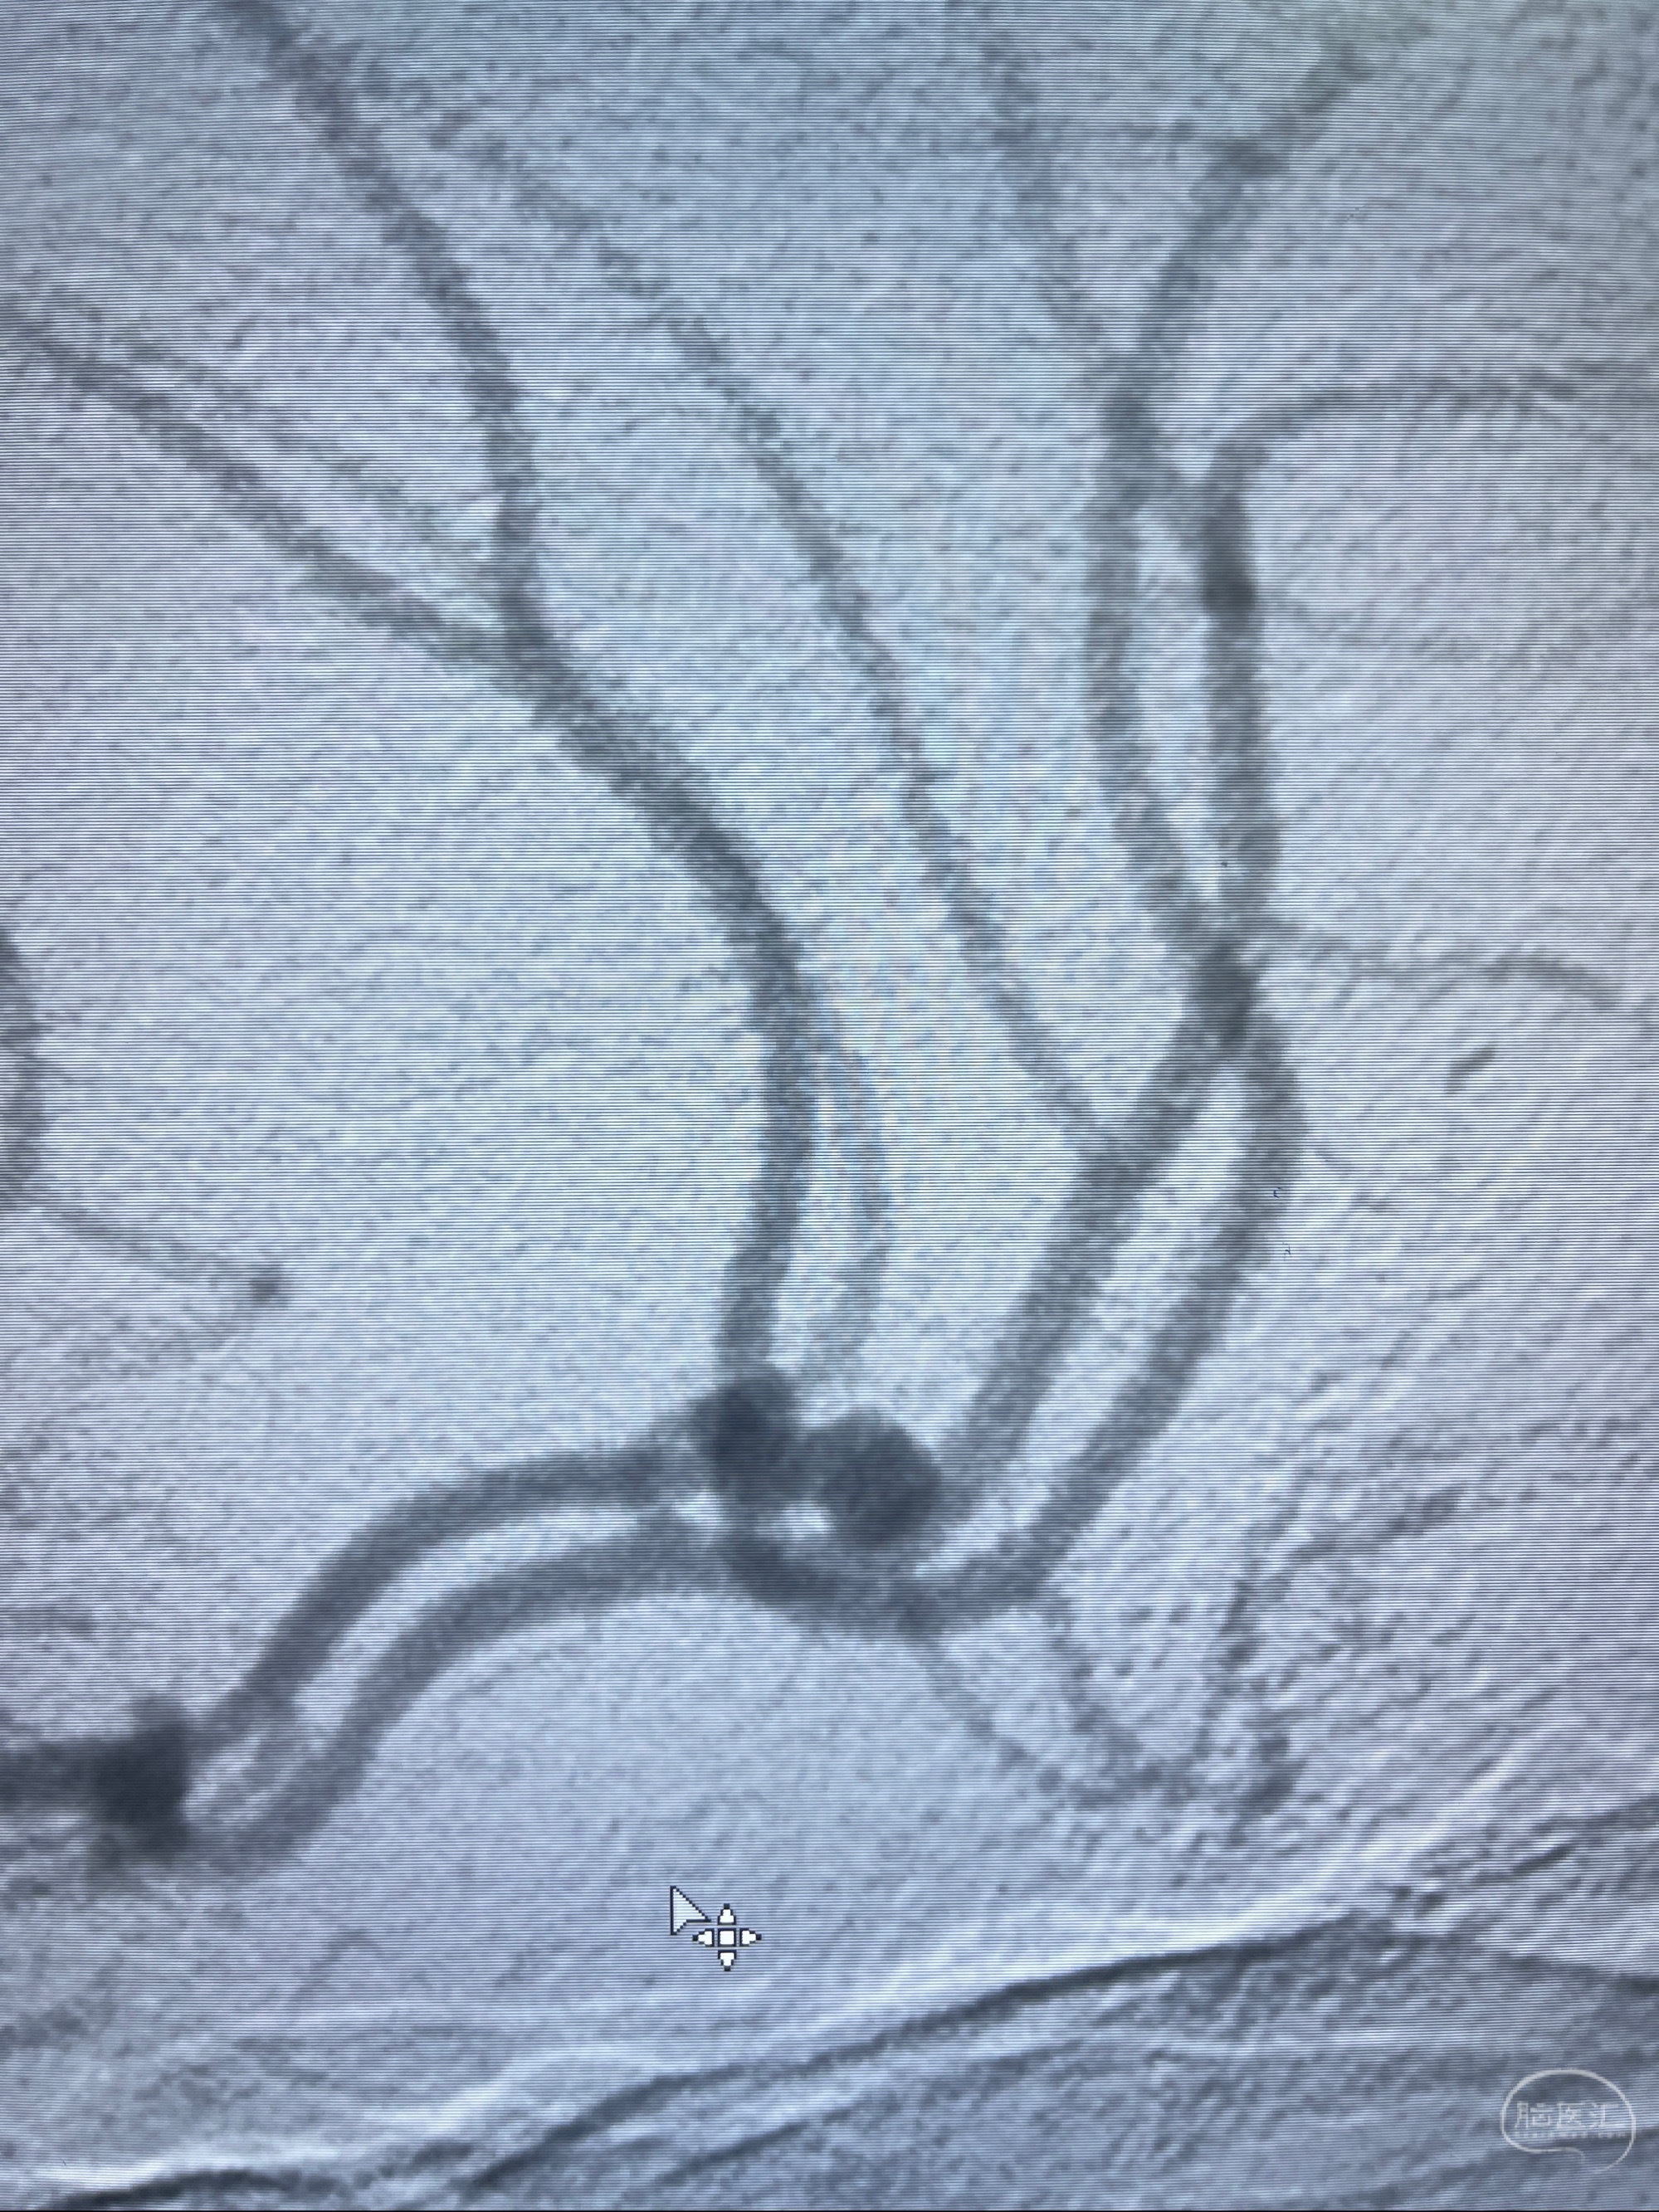

检查;2023-7-18 抚州市第一人民医院 头颈部CTA:左侧大脑前动脉A2段动脉瘤,左侧颈内动脉C4段轻度狭窄,右侧颈内动脉C6段中度狭窄

1.左侧大脑前动脉远侧段(A2-A5)动脉瘤

2023-08-23DSA:左侧前交通动脉瘤,左侧A3/4交界处多发动脉瘤